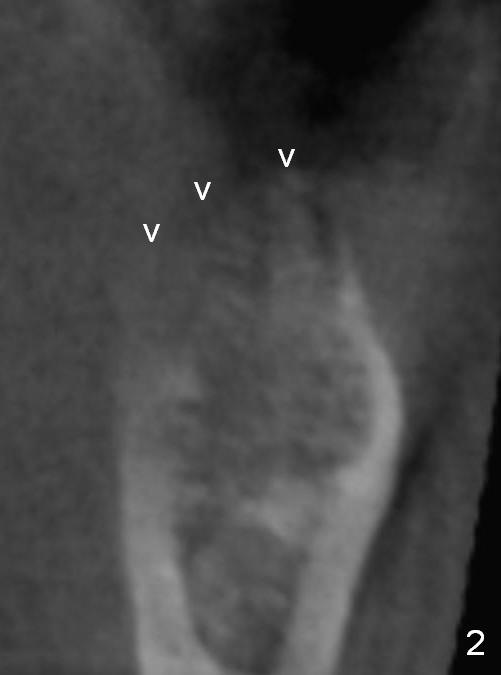

A 44-year-old black lady is a typical dental phobic. She has lost #19 for years with history of traumatic extraction. The ridge is atrophic (Fig.1). She is not comfortable with intraoral X-ray. So CBCT is taken. The coronal section shows that the bone density is low in the coronal ridge (Fig.2 arrowheads). It is difficult to determine the buccolingual width at crest; probably a 5.9x10 mm implant is appropriate (Fig.3). The most useful information from CT is height determination for the implant (Fig.4). The initial osteotomy depth is 10 mm (Fig.5); there is a large safety margin. There is a 2 mm clearance when a 4.5x12 mm implant is placed (Fig.6). Incision is sutured; a 8x4 (3) mm healing abutment is placed (Fig.7 arrowhead), followed by application of perio dressing. The latter remains stable 13 days postop thanks to the holding effect of the healing abutment (Fig.8 H). The wound has apparently healed when the dressing is removed (Fig.9). It appears that the edentulous space is extremely wide. The 4.5 mm implant may not sustain masticatory force. Limited orthodontic treatment appears to be necessary, using the implant as an anchorage to move the neighboring teeth (Fig.10 arrows). In fact the orthodontic treatment is not rendered. A crown is cemented 14 months postop. The cortical bone is thickened around the implant 15 months post cementation (Fig.11).